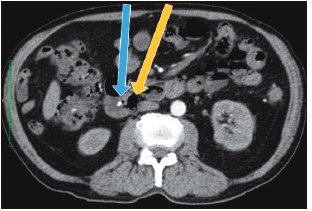

Con los hallazgos mencionados, se realizó el diagnóstico de colangitis grado II (sobre la base de los criterios diagnósticos y de severidad de las guías de Tokyo),6 y se inició tratamiento antibiótico. Posterior a las primeras 24 horas del diagnóstico, el paciente fue sometido a CPRE, en la que se identificaron tres divertículos duodenales periampulares. Debido a que la canulación fue difícil, tuvo que realizarse, durante el procedimiento, la técnica de rendez-vous (guiada por ecografía y fluoroscopía), utilizando el acceso transparietohepático para lograr el ingreso a la vía biliar. En la colangiografía, el conducto biliar se encontraba dilatado (10 mm) y no se evidenciaron imágenes por defecto de relleno. Se realizó una esfinterotomía mínima y se colocó una prótesis biliar plástica de 10 Fr x 7 cm para poder asegurar un adecuado drenaje de la vía biliar. El paciente evolucionó favorablemente. Al momento del alta no presentaba dolor abdominal, había normalizado los valores de leucocitos y PCR, y los valores de colestasis se encontraban en descenso. En los controles posteriores, el paciente presentó dolor abdominal esporádico en el CSD, pero el examen físico y los análisis de sangre no mostraron mayores alteraciones. El paciente contaba, además, con una tomografía abdominal con contraste, que no aportó información adicional a la evidenciada en la CPRM (Figuras 2 y 3).

Figura 3. Tomografía abdominal (corte axial): divertículo duodenal periampular

(flecha amarilla) y prótesis biliar plástica en el conducto biliar común (flecha

celeste).